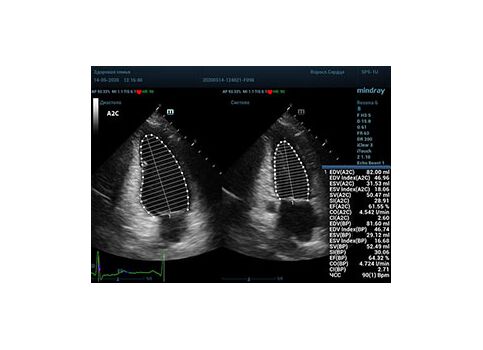

С появлением В режима реализовалась возможность визуализации всех сегментов миокарда из парастернальных и апикальных сечений. Метод Teicholtz в широкой практике сменился методом дисков. Метод дисков, или метод Simpson, позволяет разбить левый желудочек на 20 дисков, с расчетом объема каждого из них. Используя 2 перпендикулярных сечения, апикальные двух и четырех камерное, мы приближаемся к значению реального объема левого желудочка. Исследователь обводит интерфейс эндокард – кровь в фазу диастолы и фазу систолы. Линия простирается от кольца митрального клапана и до кольца митрального клапана, четко разграничивая объем желудочка от предсердия. Для достоверного изменения необходимо использовать ЭКГ канал.

Что могут предложить современные приборы? Приборы нашего времени являются мощными вычислительными машинами, способными обрабатывать полученную информацию даже без помощи человека. Система автоматического вычисления фракции выброса – AUTO EF на приборах серии Resona компании Mindray сделает все за вас. За пару секунд прибор сам отыщет нужную фазу сердечного цикла и произведёт измерение и расчеты, а также покажет график изменения объема в сердечном цикле. От Вас требуется только получить качественное 4С и 2С сечение. Впрочем, прибор всегда оставляет возможность коррекции, если доктор имеет свое мнение на расположение точек планиметрии или момента измерения по ЭКГ каналу.